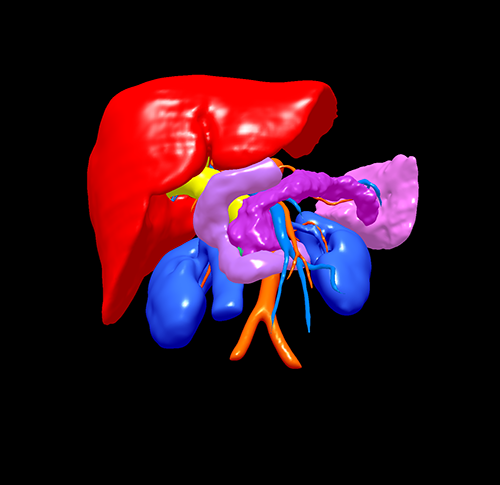

胰头癌-胰十二指肠切除